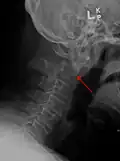

A fracture of both pedicles of the axis is termed a Hangman's fracture.

A fracture of the base of the dens as seen on plain X-ray -